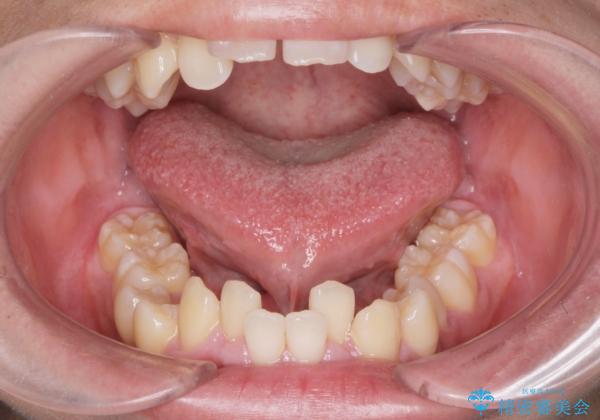

舌小帯を切りたい。

- 20代男性

- 滑舌が悪いとの事で来院。

当日に舌小帯の切除を行う事になりました。